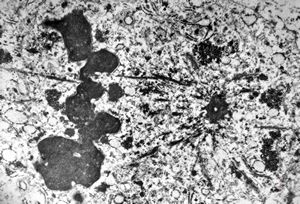

M, 62y. | mitosis … angiomatous tumor, v.s. Kaposi sarcoma

M, 62y. | angiomatous tumor, v.s. Kaposi sarcoma

M, 62y. | Weibel-Palade body - angiomatous tumor, v.s. Kaposi sarcoma